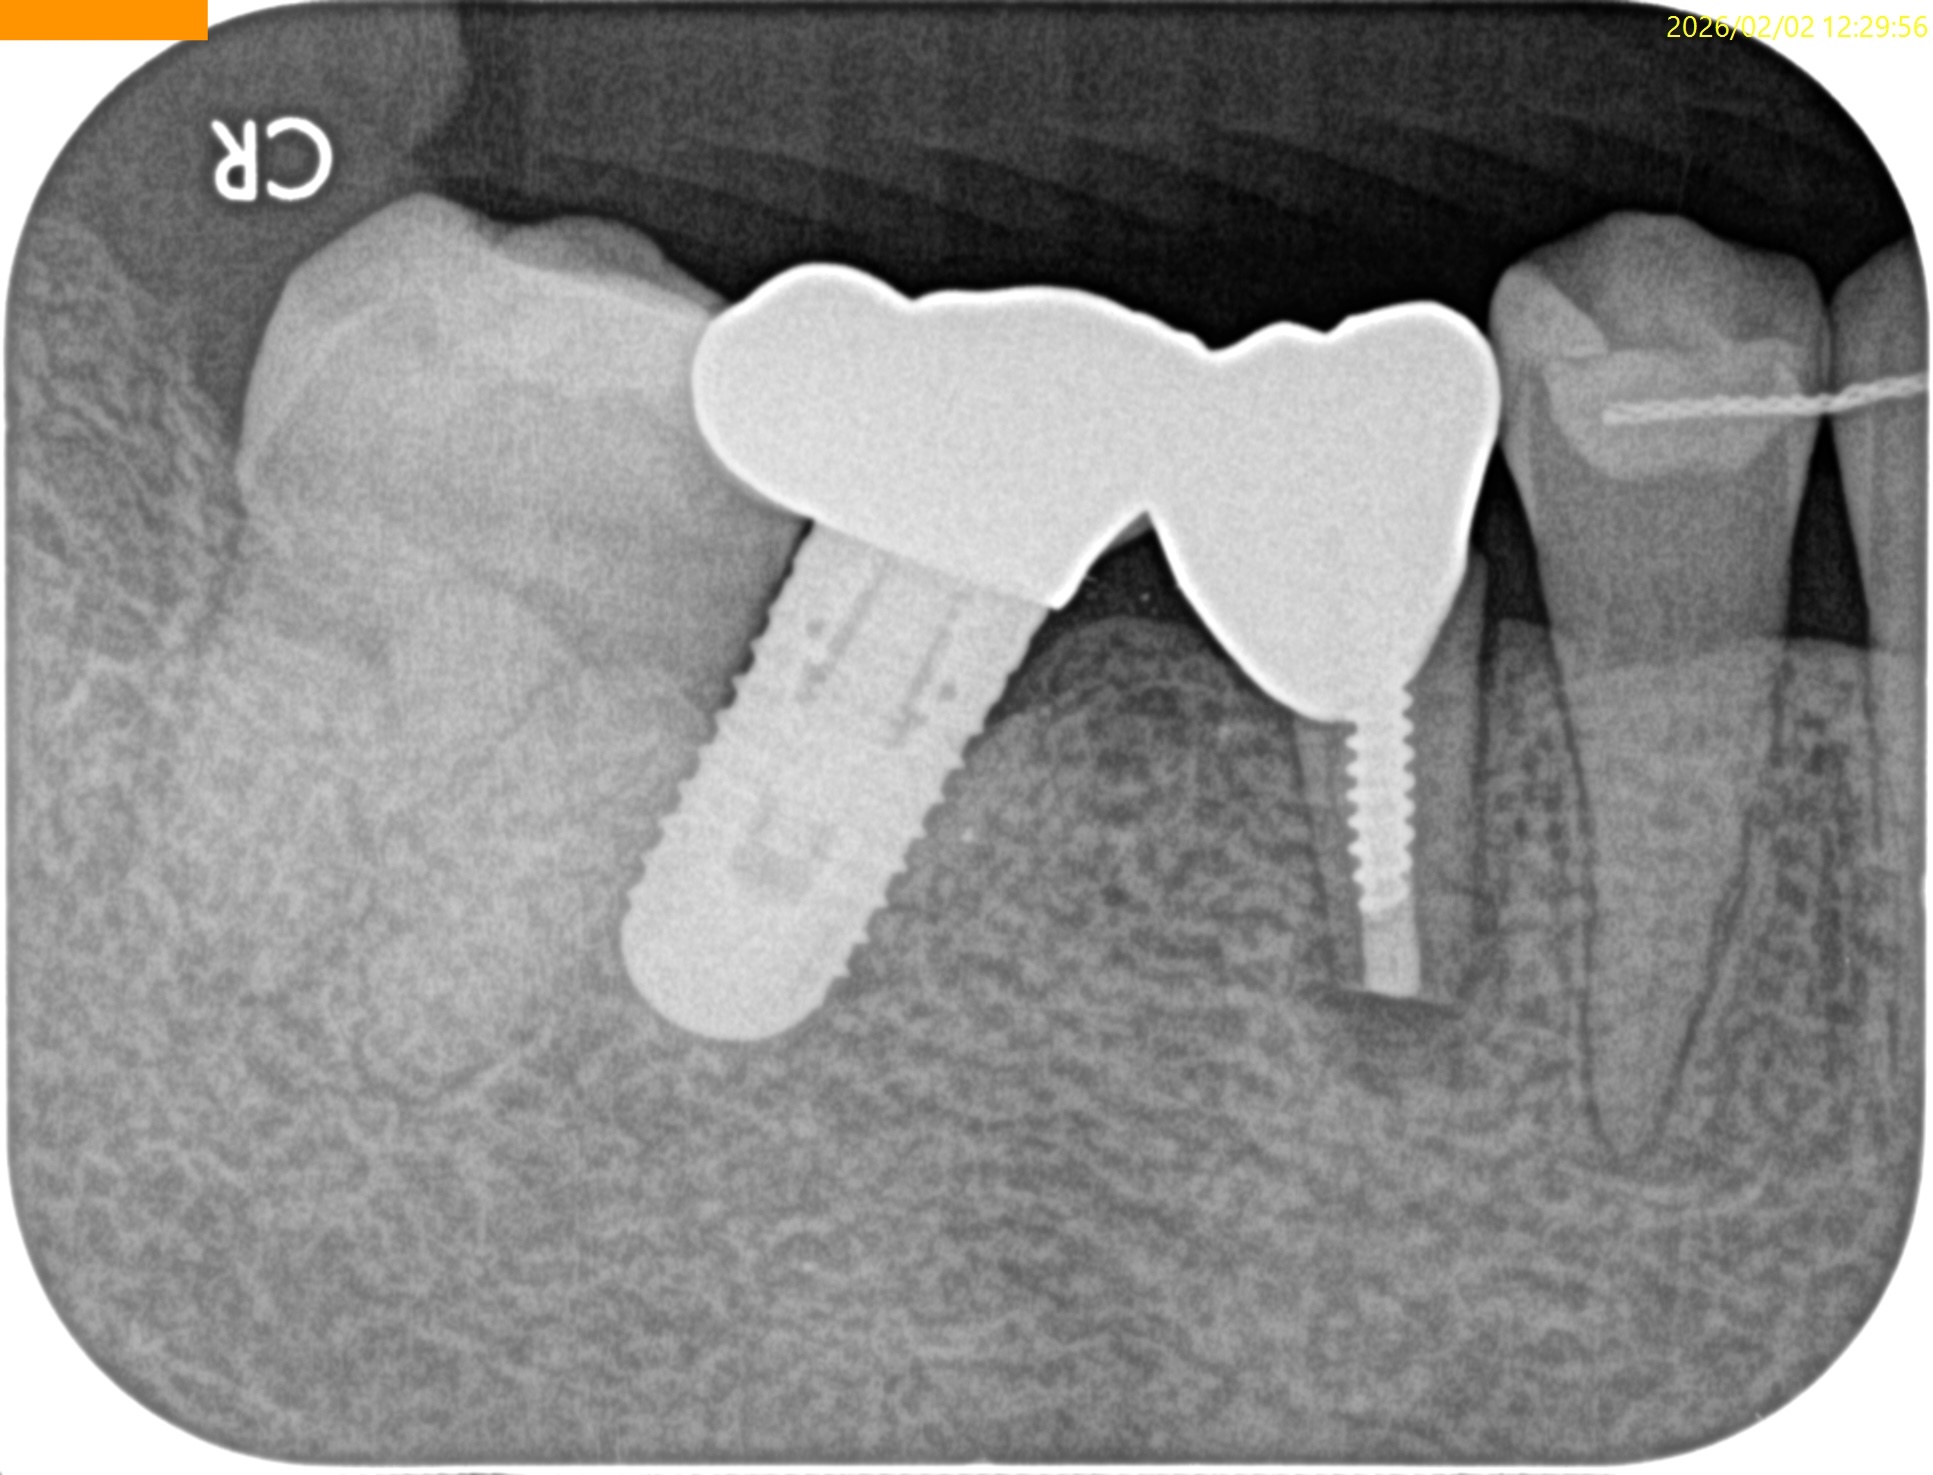

歯牙を再植した。

術後にPA, CBCTを撮影した。

問題はないだろう。